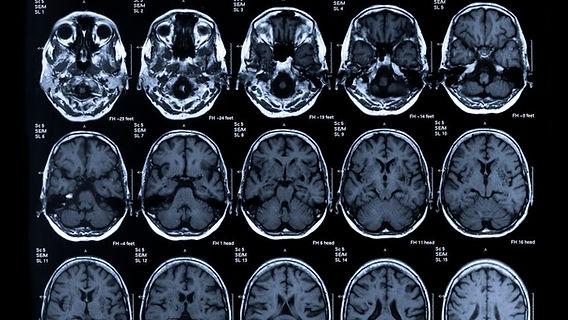

MRI Scan

- Advanced imaging for soft tissues, brain, spine, joints, and musculoskeletal system